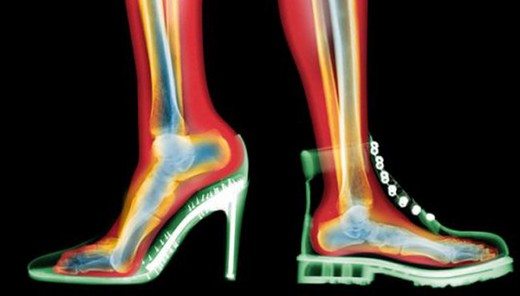

Mağazadan milyonlarca kişi kimi için süs kimi için ihtiyaç malzemesi olan topuklu ayakkabılar mağazasından yüzlerce liraya alınıyor ama uzman isim uyardı: vatandaş mağdur oluyor. Kadınların vazgeçilmez tutkusu topuklu ayakkabı, çeşitli sağlık sorunlarına yol açıyor diyerek Ortopedi ve Travmatoloji Uzmanı Op. Dr. Mutlu Güngör uyarılarını kamuoyu ile paylaştı. Topuklu ayakkabı, ayak bileği burkulması ve ayak tabanında ağrıya yol açıyor.

Kadınların vazgeçilmez tutkusu topuklu ayakkabı, çeşitli sağlık sorunlarına yol açıyor.

Ortopedi ve Travmatoloji Uzmanı Op. Dr. Mutlu Güngör, topuklu ayakkabıların sadece ayaklara değil, vücuda da ciddi zararı olduğunu belirtiyor.

Ayakkabılarda 4.5 santimden fazla olan topuğun anatomik sistemi bozduğunu söylüyor.

"Topuk 4.5 santimden yüksek olursa ağırlık ve basınç öne doğru kayar.

Özellikle sivri burunlu ve topuklu ayakkabı giyen kadınlarda başparmakta şekil bozukluğu ve iç yanında ağrılı kemik çıkıntısı oluşumu ve nasır meydana gelir. Bu nedenle topuğun abartılmaması gerekir" uyarısında bulunuyor.(takvim)